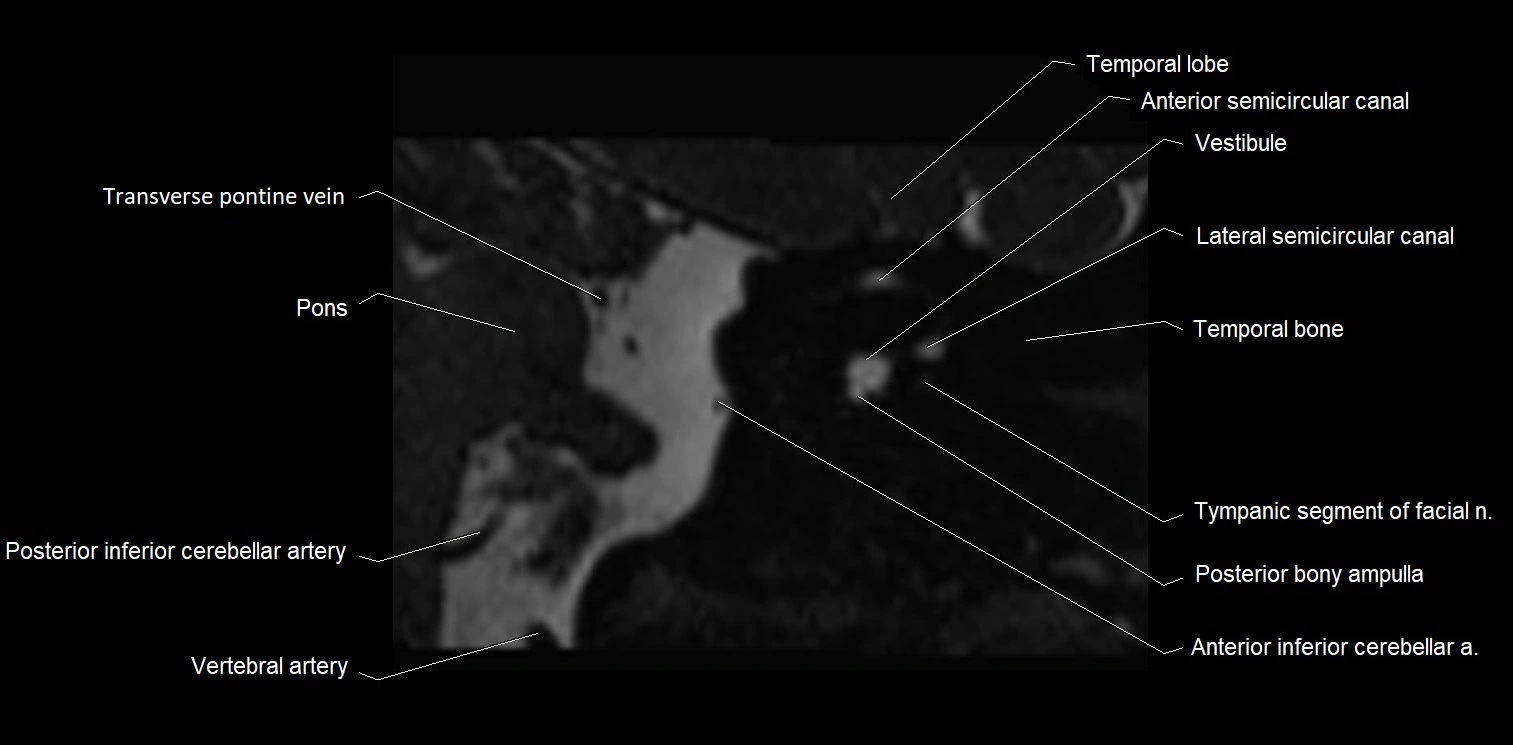

MRI Appearance

• The abducens nerve is a small, thin, linear structure

• Best visualized on high-resolution T2-weighted 3D MRI sequences (e.g., FIESTA or CISS)

• Seen as a hypointense (dark) line running from the brainstem at the pontomedullary junction, traversing the prepontine cistern, and entering Dorello’s canal under the petrosphenoidal ligament, then into the cavernous sinus, and finally the orbit

• May be challenging to visualize in standard MRI due to its small size

• Pathology may be inferred by absence, displacement, or enhancement of the nerve